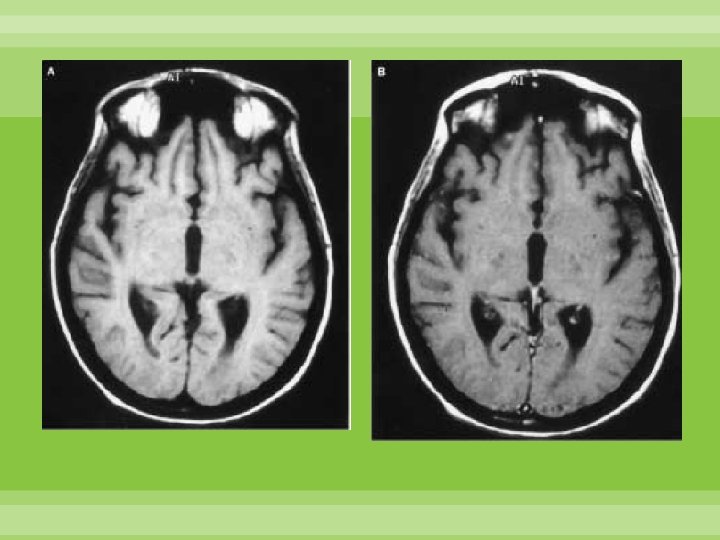

Encefalopatía Hipertensiva Microhemorragia Disfunción endotelial Alteración barrera hematoencefalica Edema cerebral

Leucoencefalopatía posterior reversible Secundario a vasoconstricción sostenida Disminución de inervación simpática en la circulación posterior. Reversible Cefalea súbita, pérdida de la visión, náusea, vómito, alteración del estado de alerta Secuelas asociadas a infarto o hemorragia Schwedt, Matharu, Dodick Thunderclap headache Lancet Neurol 2006; 5: 621– 31

Edema vasogénico en sustancia blanca posterior: parietal y occipital, puede extenderse a ganglios basales, tallo y cerebelo Schwedt, Matharu, Dodick Thunderclap headache Lancet Neurol 2006; 5: 621– 31